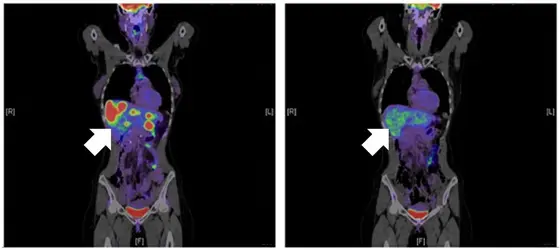

Das HIV-Medikament Maraviroc blockiert das Oberflächeneiweiß CCR5. Dadurch werden die Makrophagen in der Leber aktiviert die Metastasen zu bekämpfen. Die Metastasen in der Leber (links) verschwanden bei diesem Pateinten nach Behandlung (rechts).

Nach den präklinischen Experimenten konnten die Forscher den Mechanismus in einer Phase-I-Studie mit 14 Patienten bestätigen und einen Rückgang einzelner Metastasen beobachten. Die Studie wurde von der Dietmar Hopp Stiftung gefördert. „Die Daten der klinischen Studie zeigen eine sehr gute Verträglichkeit des HIV-Medikaments. Aber auch das Ansprechen in Kombination mit einer Chemotherapie ist vielversprechend“, berichtet Prof. Dirk Jäger, Ärztlicher Direktor am NCT und Sprecher des Forschungsschwerpunkts Tumorimmunologie am DKFZ. „Gerade für Darmkrebspatienten könnten neue Immuntherapien die Behandlungsmöglichkeiten massiv verbessern“, fügt Prof. Markus W. Büchler hinzu, Geschäftsführender Direktor der chirurgischen Universitätsklinik in Heidelberg.